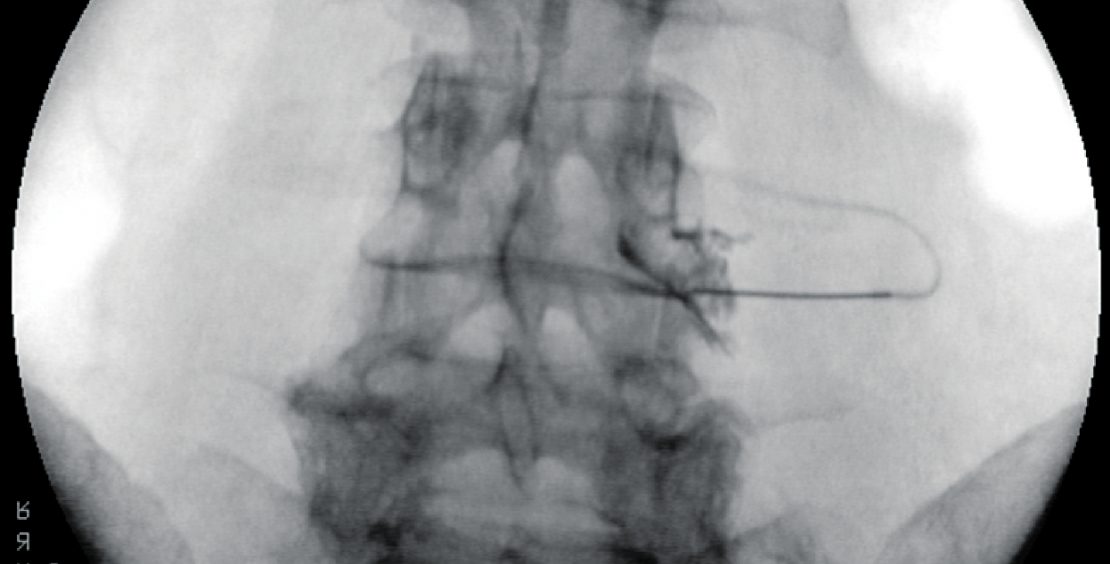

Zur Diagnostik werden aufgrund der hohen Rate falsch-positiver Ergebnisse bei der ersten Intervention zwei Interventionen zu unterschiedlichen Zeitpunkten, sinnvollerweise mit unterschiedlich lang wirkenden Lokalanästhetika (zum Beispiel Lidocain und Bupivacain) durchgeführt (11). Vor Injektion des Lokalanästhetikums wird zur definitiven Lagekontrolle sowie zum Ausschluss einer intravasalen Position der Nadelspitze Röntgenkontrastmittel injiziert (Abb. 1). Nach positiver Diagnostik kann unter therapeutischem Aspekt sowohl die perkutane funktionelle Denervation (Radiofrequenztherapie) als auch die transforaminale Steroidinfiltration zum Einsatz kommen, wobei die Durchführung grundsätzlich der Durchführung der diagnostischen Blockaden sehr ähnlich ist. Für die Wirksamkeit der Radiofrequenztherapie besteht etwas Evidenz (12), die Evidenz bezüglich Steroidinfiltrationen ist nicht eindeutig belegt (13).